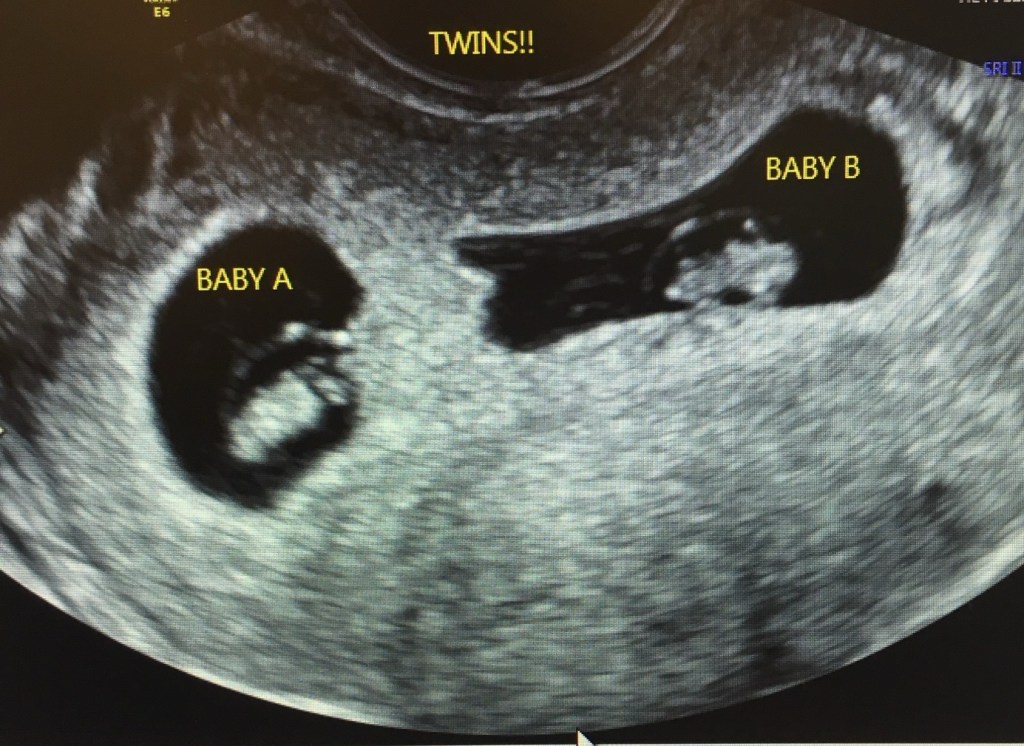

To everyone’s joy and amazement, both embryos took. I was officially pregnant with twins!